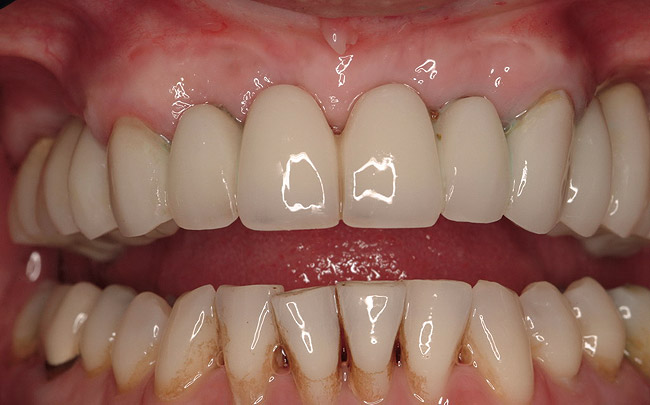

Figure 15  Fixed provisional bridge supported by the maxillary second molars and canines.

Figure 15